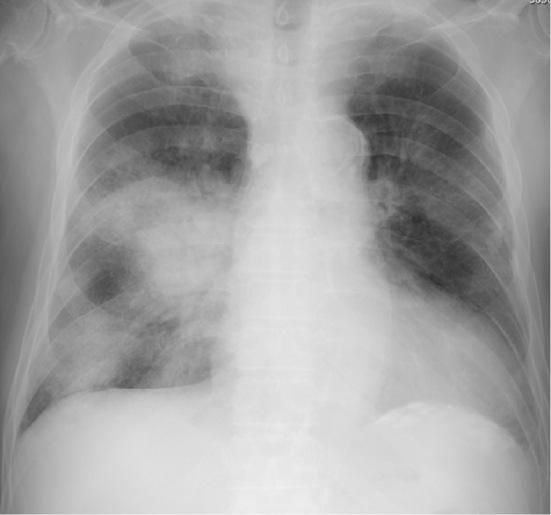

A 73-year-old man receiving hemodialysis and antiplatelets was admitted with a mild case of COVID-19. Heparin was added, and iliopsoas hemorrhage developed. He was successfully treated by interventional radiology. A 76-year-old man receiving hemodialysis and antiplatelets was admitted with mild COVID-19. Heparin was added, and iliacus hemorrhage developed. Despite heparin discontinuation, he died of worsening pneumonia. A 74-year-old man undergoing hemodialysis was admitted with severe COVID-19. Gastrointestinal bleeding developed during continuous hemodiafiltration with heparin. Upon switching to nafamostat and increasing the dose, iliopsoas hemorrhage developed. Despite interventional radiology, he died of infectious complications. Attention to hemorrhagic complications is therefore needed in patients with COVID-19.

一位 73 岁男性,正在接受血液透析和抗血小板治疗,因 COVID-19 轻度感染入院。给予肝素后,发生了髂腰肌血肿。通过介入放射学成功治疗。一位 76 岁男性,正在接受血液透析和抗血小板治疗,因 COVID-19 轻度感染入院。给予肝素后,发生了髂肌血肿。尽管停用了肝素,但他仍因肺炎恶化而死亡。一位 74 岁男性,正在接受血液透析,因 COVID-19 重度感染入院。在使用肝素进行连续性血液透析滤过过程中出现胃肠道出血。改为使用那屈肝素并增加剂量后,发生了髂腰肌血肿。尽管进行了介入放射学治疗,但他还是死于感染性并发症。因此,COVID-19 患者需要注意出血并发症。